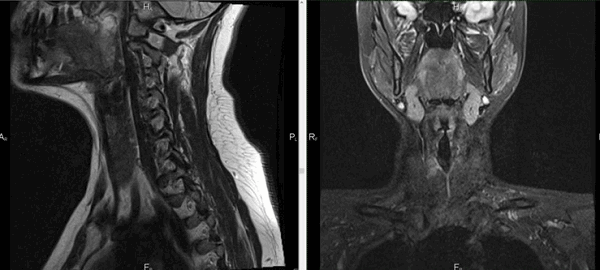

Рисунок 1,2. МРТ мягких тканей шеи (Т2-ВИ и Т1-fs-ВИ контрастное усиление). Патологических образований в структуры щитовидной железы не выявлено.

Снимки МРТ мягких тканей шеи

Мягкие ткани шеи на МРТ